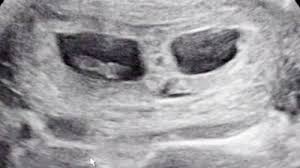

Besonderheiten beim Ultraschall in der 8SSW In der 8Schwangerschaftswoche ist der Kopf noch größer als der gesamte Körper des Embryos. In Ultraschall ist immernoch keine fruchthöhle zu sehen. Das baby ist in der 8 woche 2-3 cm groß und geschlecht wird man sicherlich nicht erkennen können.

In dieser Woche kommt es bei Deinem Kind zum sogenannten physiologischen Nabelbruch und die Verknorpelung seiner zukünftigen Knochen beginnt. Schwangerschaftswoche der Embryo ist jetzt etwa sechs Wochen alt können Sie im Ultraschall erste Ansätze von Fingern und Zehen sehen. Dies sieht gewiss etwas unförmig aus wirkt aber zuckersüß.